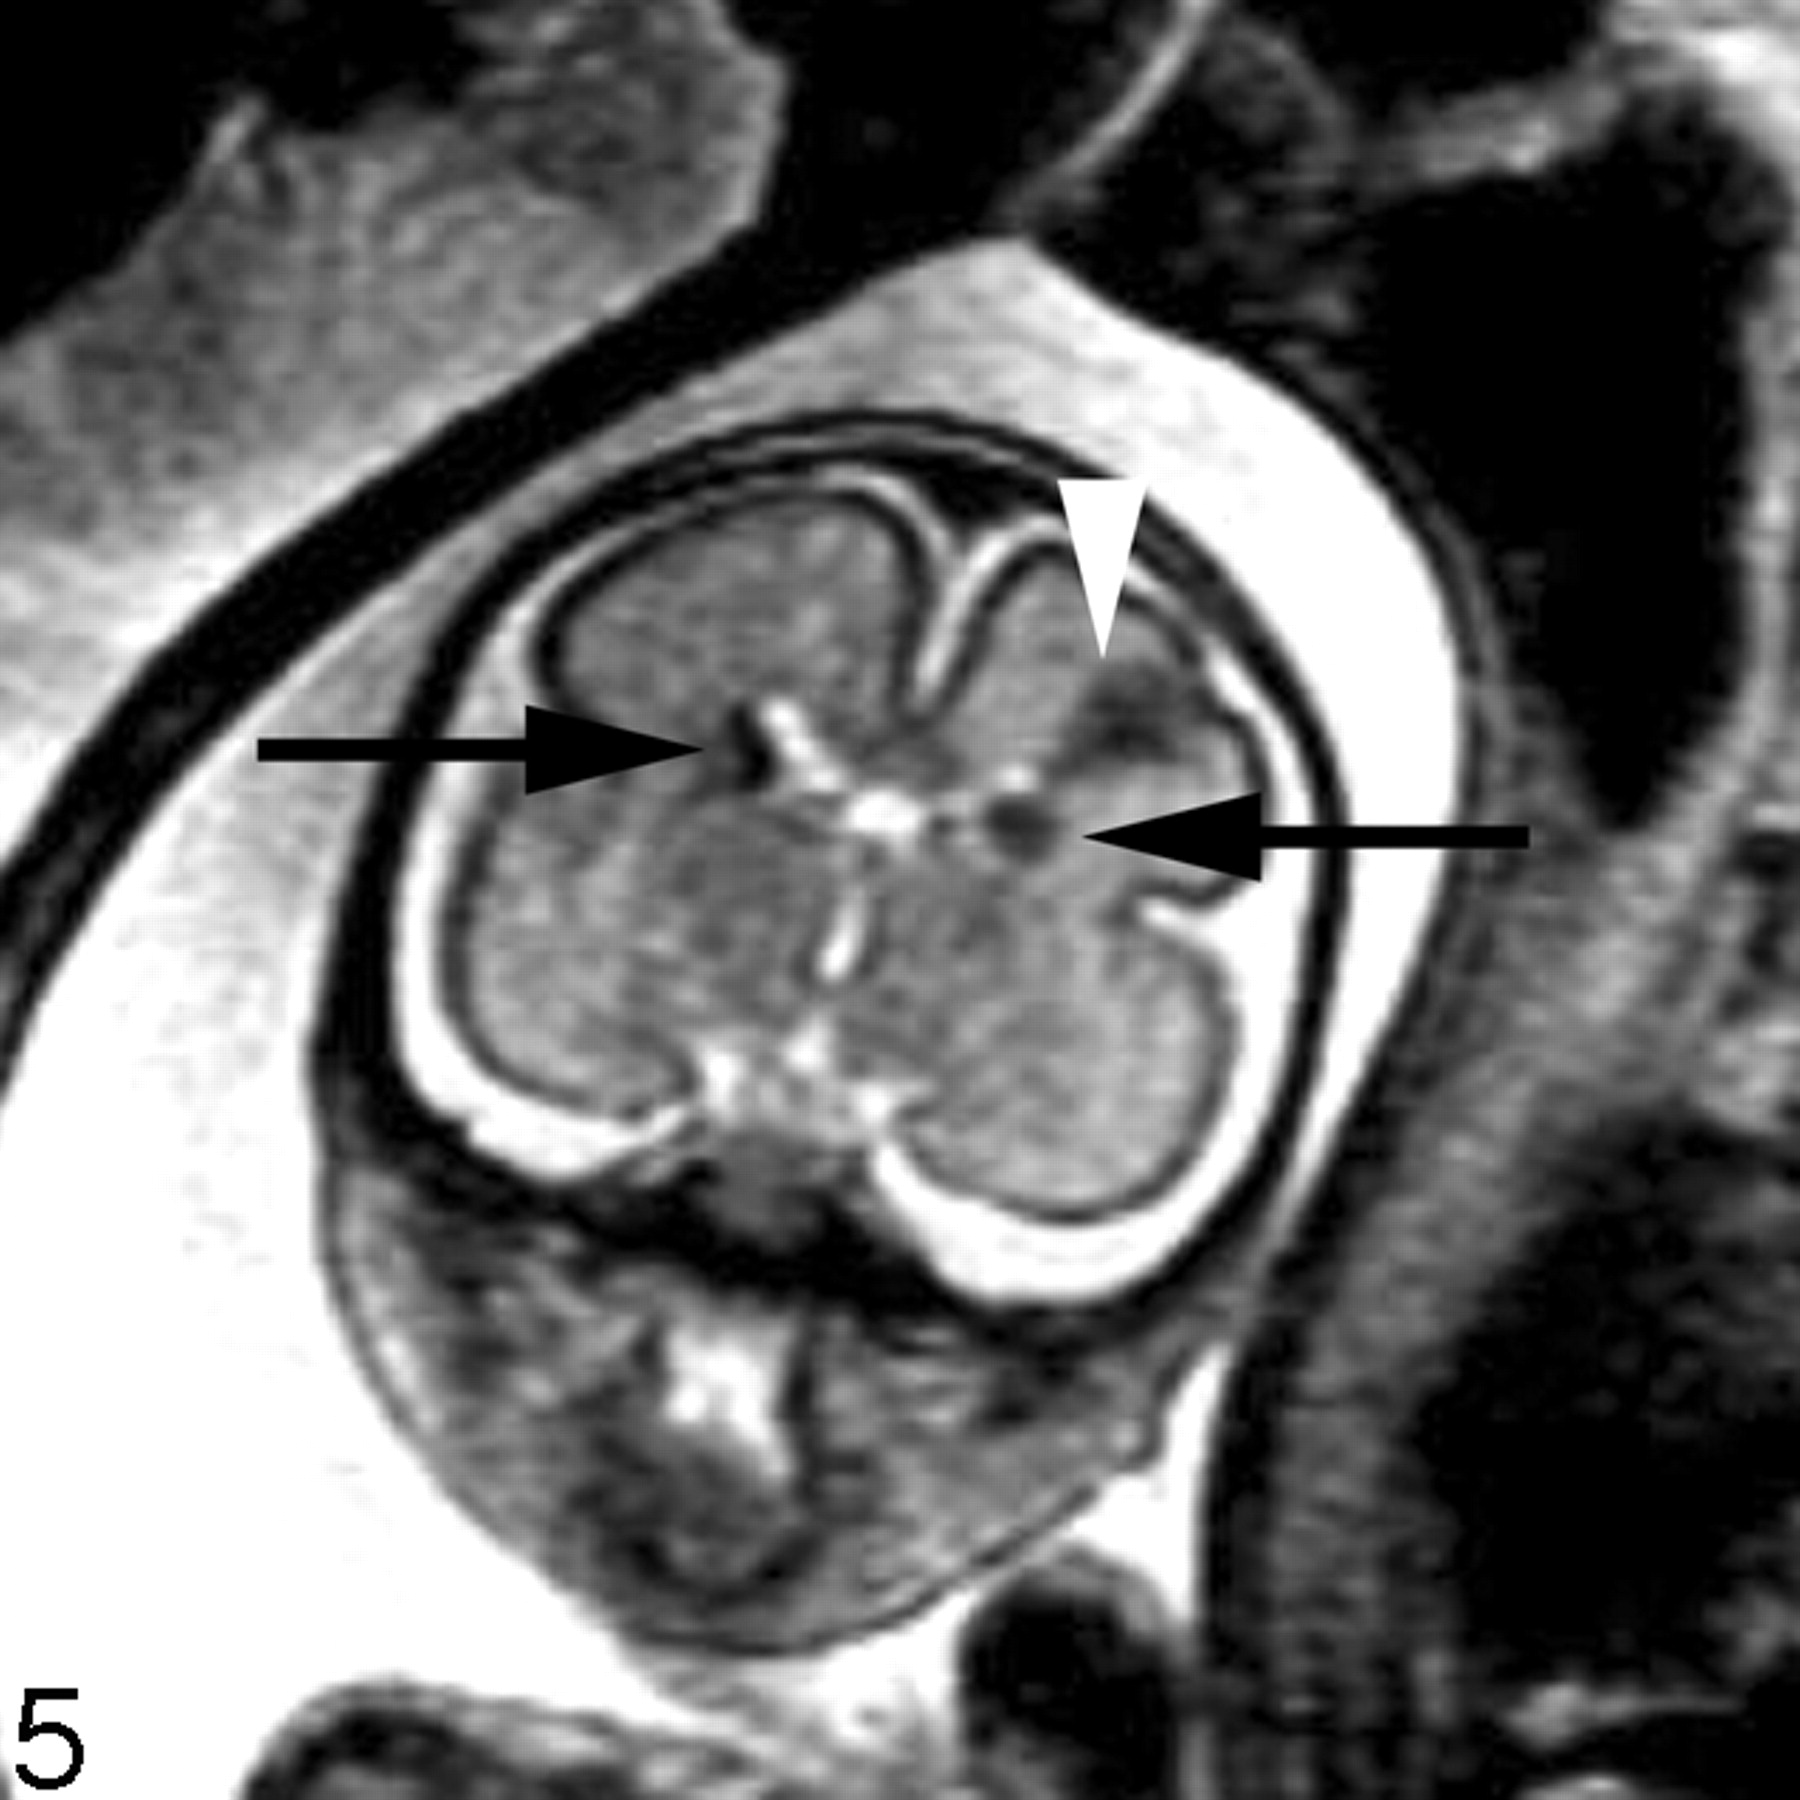

In our experience, fetal MR imaging is especially useful in detecting malformations of cortical development in fetuses with sonographically isolated ventriculomegaly. When interpreting fetal MR images in this clinical setting, the margins of the lateral ventricles should be carefully scrutinized for any areas of nodularity that may represent periventricular nodular heterotopia. Such nodules are isointense to the germinal matrix (Fig 4). Periventricular nodular heterotopia, however, are indistinguishable from the subependymal nodules present in tuberous sclerosis, and other manifestations of tuberous sclerosis, such as transmantle dysplasias, cortical tubers, and cardiac rhabdomyoma, should be sought when ventricular nodularity is identified (Fig 5). Cortical malformations, such as polymicrogyria, can be identified by noting alteration of the normal sulcation pattern for a fetus’ particular gestational age (Fig 6A); they may be identified as too many sulci in a less mature fetus or as too few or abnormally deep or abnormally located sulci in a more mature fetus. The identification of malformations of cortical development in the setting of ventriculomegaly should raise the possibility of a genetic (including metabolic disturbances) or an infectious cause of the ventriculomegaly.

Coronal SS-FSE T2-weighted image of a 26-week-old fetus demonstrates several hypointense nodules along the margins of both lateral ventricles (arrows). The nodules are somewhat similar to those in Fig 3 (though much larger in this example). A hypointense wedge-shaped area is also seen extending from the margin of the left lateral ventricle to the developing cortex (arrowhead), consistent with transmantle dysplasia. The fetus also had a cardiac rhabdomyoma (not shown). Findings are consistent with tuberous sclerosis.